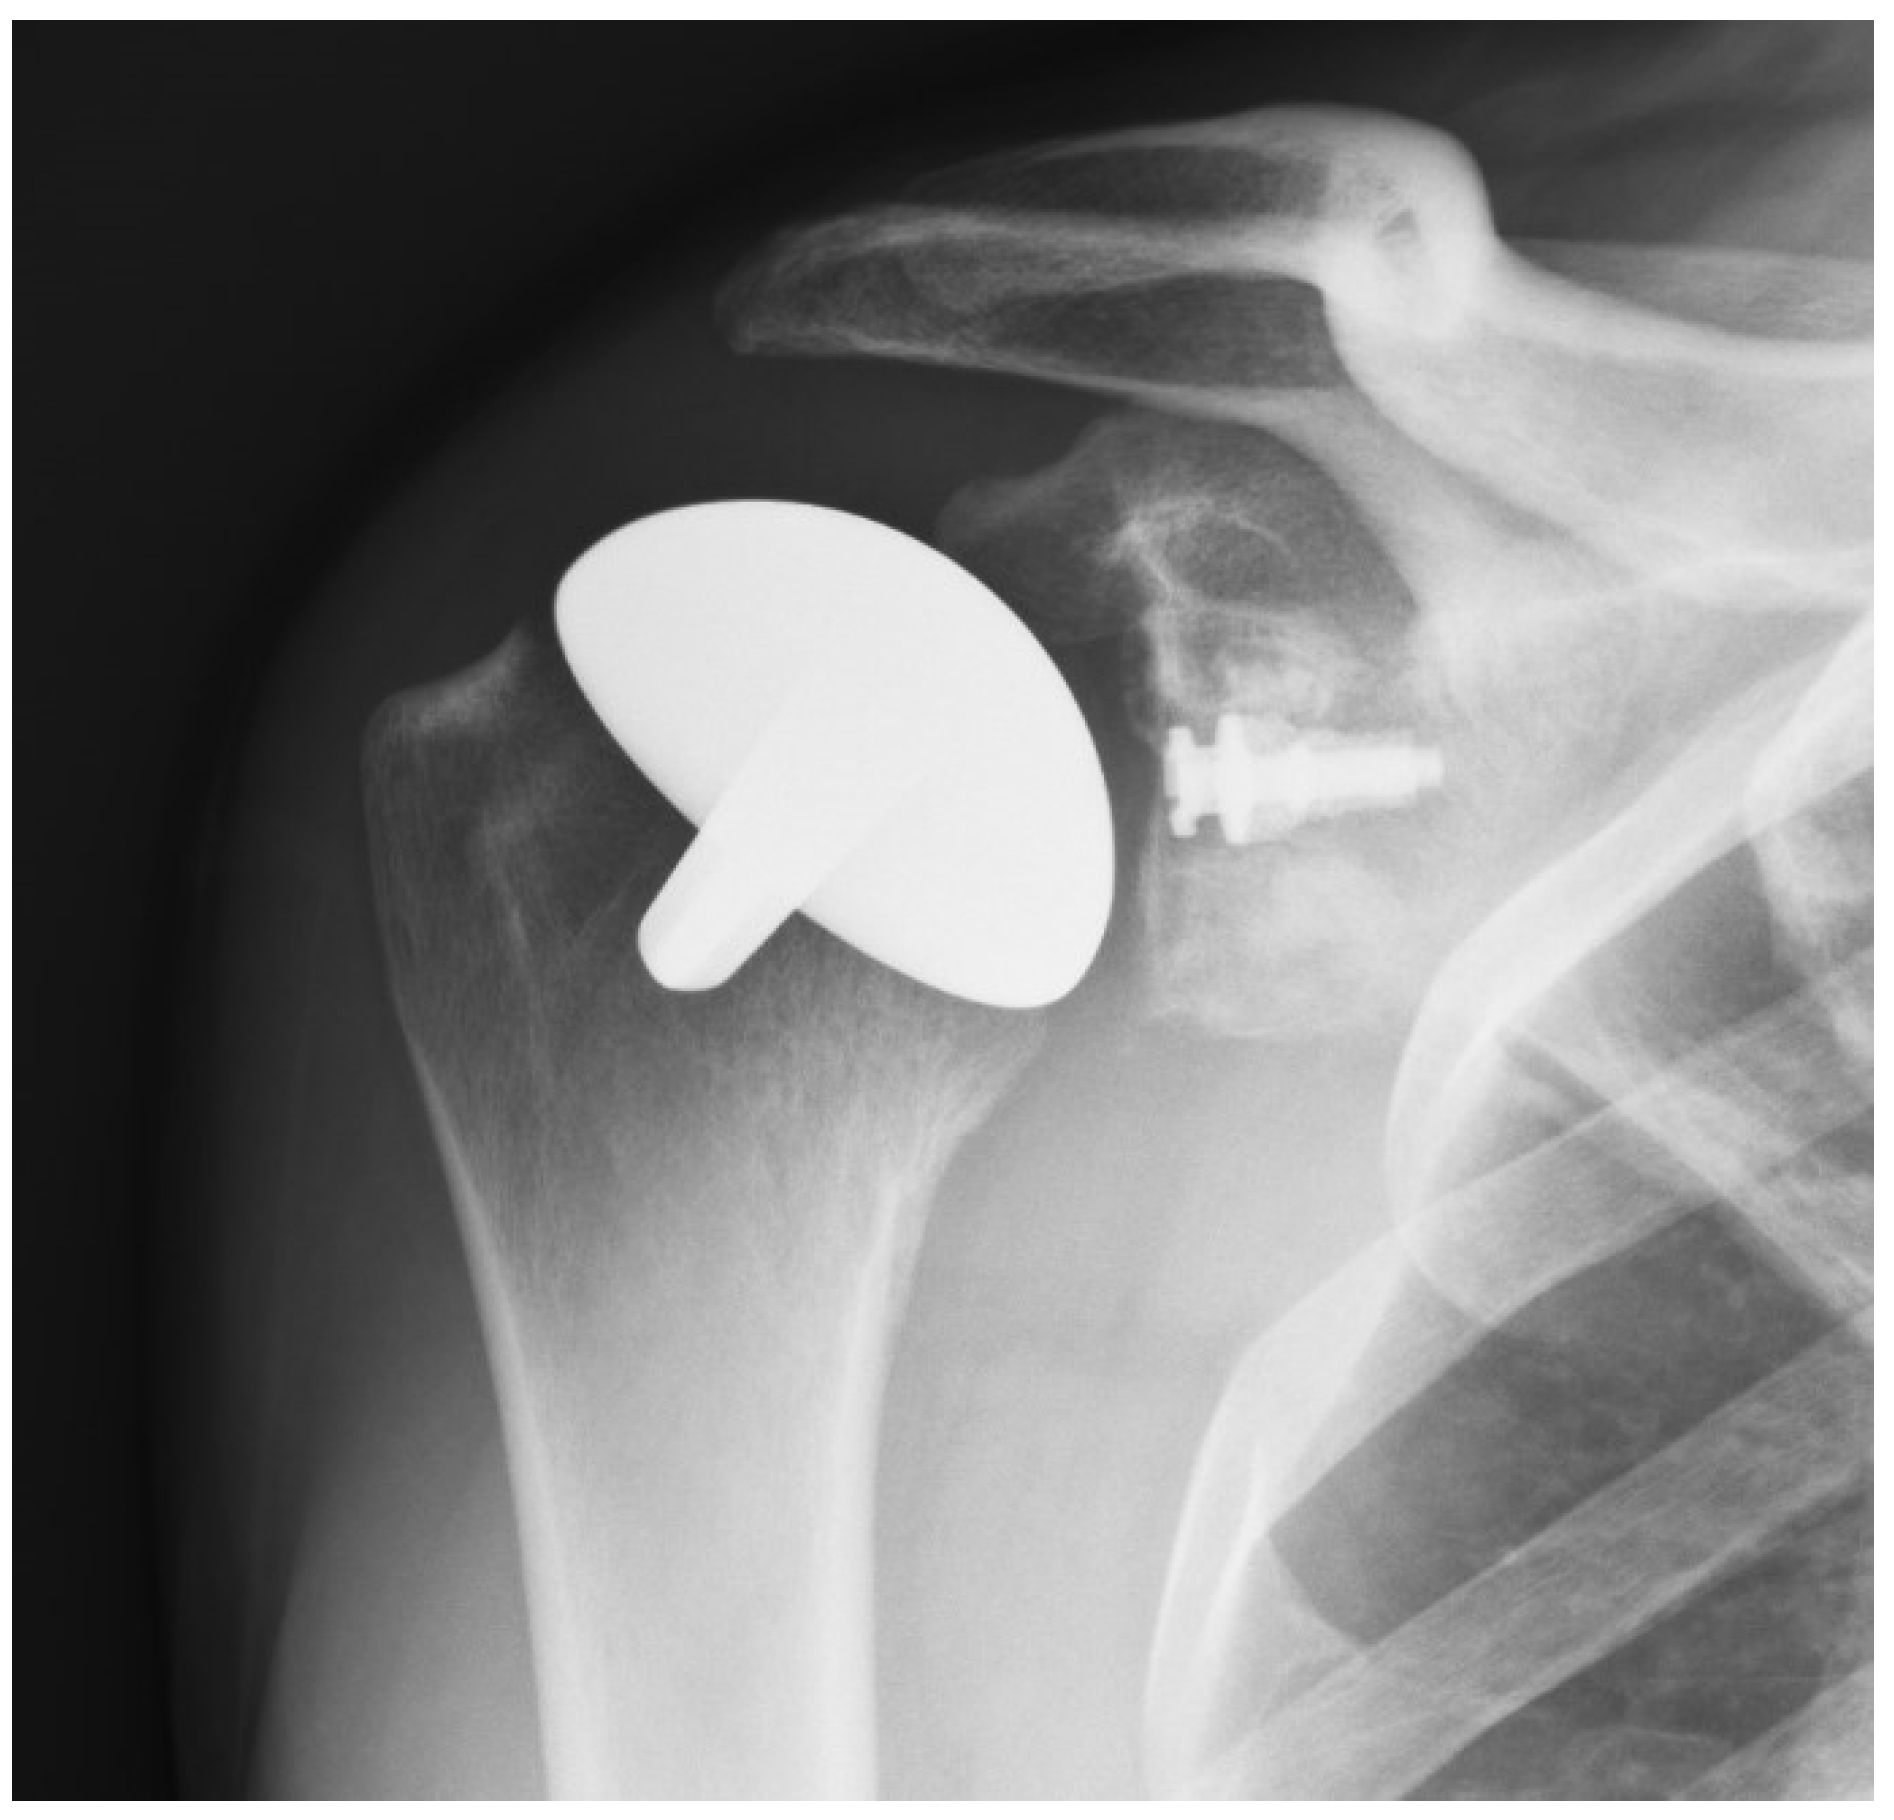

In the majority of cases, the humeral resurfacing prosthesis will articulate directly with the preserved glenoid cartilage [8,9,10,11,12,13,14,15]. Therefore, the smoothest possible surface is necessary. Ceramic coating the implant is the best method to achieve this goal (Figure 1).

Titanium nitride (TiN) has high hardness and a low friction coefficient. It has been shown to be efficient in reducing the wear of cutting tools. It has been cleared by the Food and Drug Administration as an implant bearing surface and coating (510K 93122). It has much less wear compared to the cobalt chromium implants that are typically used for shoulder replacement and other resurfacing implants. In addition to reduced wear, there are no metal ions released into the tissues and, therefore, no chance of metal sensitivity or an allergic reaction [18,19,20]. The glenoid component, when needed, is either cemented or porous-backed polyethylene [10,15] (Figure 2).

Figure 2. AP radiograph of a shoulder resurfacing with a polyethylene glenoid resurfacing component.